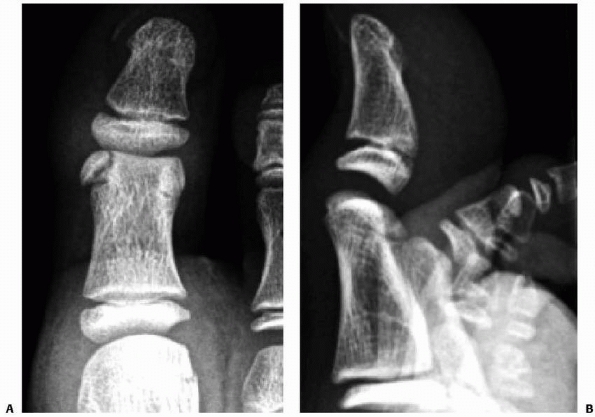

weight. An example would be a fall backwards while the foot was pinned

falls backward while the forefoot is fixed to the ground by a heavy